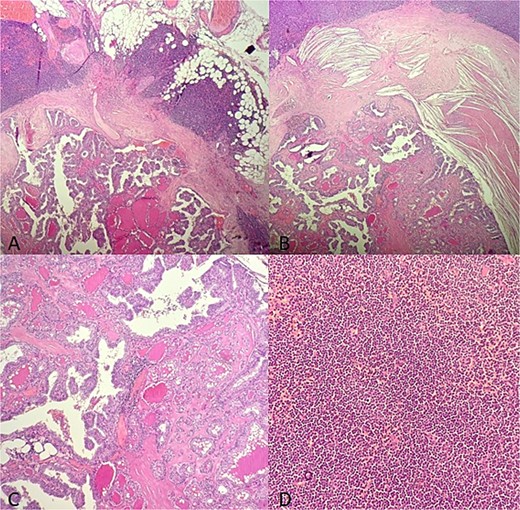

A 58-year-old man who was diagnosed with a stable and indolent SLL for 4 years presented with cervical mass enlargement for 7 months. Physical examination revealed a right, 2.5 cm, indurated painless spinal lymph node and a left 2 cm painless jugular cervical lymph node. On cervical ultrasound, multiple suspicious cervical lymph nodes and three thyroid nodules were discovered (8.5 mm EUTIRADS3 in the right lobe and 2 nodules of 5 and 6 mm in the left lobe EUTIRADS4). A fine needle aspiration (FNA) of the left thyroide nodules was performed and concluded to a Bethesda IV follicular neoplasm. Likewise, a FNA of the lymph node was carried out and revealed a monomorphic population of lymphocytes consistent with a SLL. The patient underwent total thyroidectomy with cervical lymphadenectomy. Microscopic examination concluded to multifocal PTC of the left and right lobes. The three nodules were classified pTa with no extra-thyroid extension, vascular or lymph nodes invasion. A 100 m Ci complementary radio-iodine therapy was performed and post-treatment control scintigraphy was negative. The postoperative thyroglobulin levels showed a decrease from 6.8 ng/ml (Day 7) to 1.4 ng/ml (24 months). The follow-up iodine scintigraphy performed at 2 years revealed no specific fixation. However, an increase in thyroglobulin levels (5.8 ng/ml) was observed while anti-thyroglobulin antibody was negative (<6.4 UI/ml). A cervical ultrasound revealed diffuse bilateral lymphadenopathy related to the known hematologic disorder, with lymph nodes in right level IV (20 × 9 mm) and right level VIb (10 × 5 mm) that could be of thyroid origin. A FNA of this lymph node was performed and concluded to SLL. However, the thyroglobulin level in the aspirated fluid was elevated. A cervical lymph node dissection was performed. Microscopic examination revealed lymph node involvement by PTC developed on a lymphomatous background (Fig. 1). The immunohistochemistry analysis showed diffuse and positive staining of the lymphomatous background for CD20, CD23, and CD5 which was consistent with SLL (Fig. 2). The thyroglobulin level decreased post-operatively (0.3 ng/ml). Complementary treatment with 100 mCi radio-iodine therapy was performed. The patient also developed a nasopharyngeal involvement of his SLL and was started on chemotherapy. At 1 year after lymph node dissection, thyroglobulin is negative and the scintigraphy showed no specific fixation.

Microscopic findings (A–B): HE X 10: A papillary thyroid carcinoma metastasis into a lymph node involved with a small lymphocytic lympha extending beyond the adipose tissue; (C): HE X 20: Papillary and follicule structure lined with cells showing papillary nuclear atypia; (D): HE X 20: Diffuse small cell lymphoma proliferation.